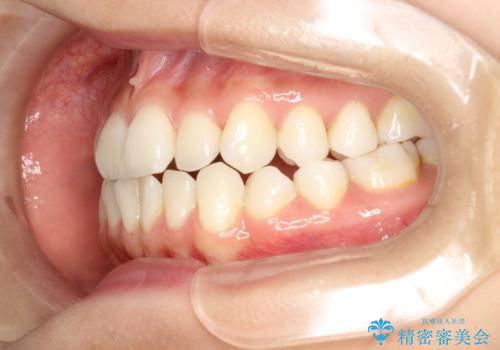

軽度の前歯のガタガタをインビザラインでの目立たない矯正

- 前歯のガタガタを主訴に来院されました。

軽度であったため、枚数制限のあるタイプのインビザラインのプランで治療することとしました。

軽度のガタガタを目立たずに手軽に矯正できるのもマウスピース矯正の魅力といえます。